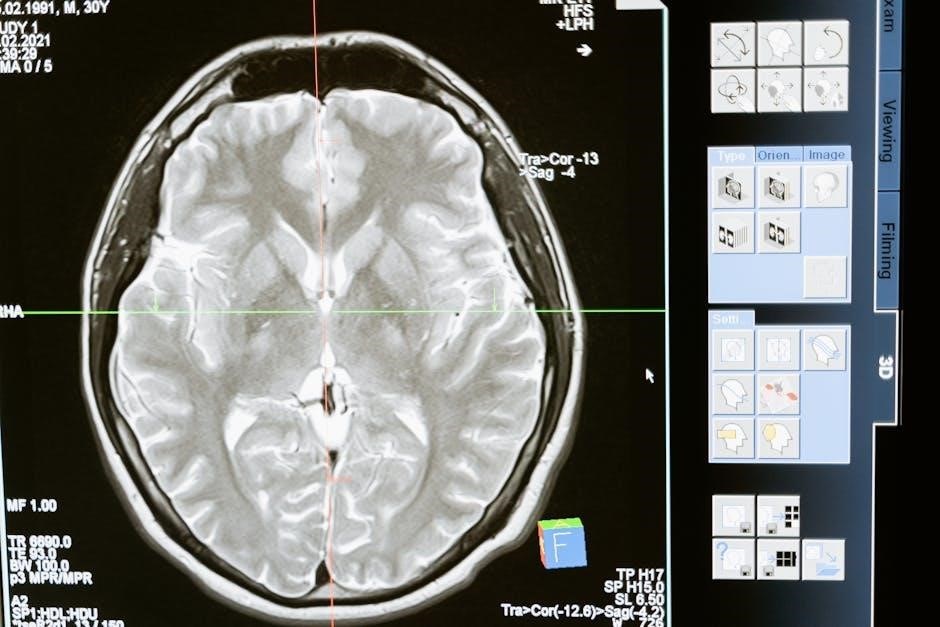

What distinguishes MRgFUS is the integration of real-time MRI thermometry. This allows clinicians to accurately monitor temperature changes during the procedure, ensuring precise targeting and minimizing damage to surrounding tissues. The MRI provides detailed anatomical visualization, guiding the ultrasound beams with exceptional accuracy.

MRgFUS combines focused ultrasound energy with real-time MRI guidance, enabling precise targeting of brain structures like the globus pallidus and subthalamic nucleus for treatment.

The Role of MRI in Guiding the Procedure

Magnetic Resonance Imaging (MRI) is absolutely integral to the success and safety of MRgFUS, serving far beyond simple visualization. It’s not merely used to identify the target brain structure – the globus pallidus or subthalamic nucleus – but actively guides and monitors the entire procedure in real-time. MRI provides high-resolution anatomical images, allowing for precise targeting of the intended focal point.

However, its most critical function is MRI thermometry. This technique allows clinicians to continuously measure temperature changes within the brain tissue as the focused ultrasound energy is delivered. This real-time temperature monitoring is paramount to ensure the therapeutic effect is achieved – creating a lesion – without causing unintended damage to surrounding healthy tissue.

The MRI’s ability to visualize the temperature distribution allows for precise control of the ultrasound parameters, adjusting power and focus as needed. This feedback loop, combining ultrasound delivery with continuous MRI monitoring, is what distinguishes MRgFUS as a highly targeted and safe non-invasive treatment option for cervical dystonia.

MRI Thermometry and Real-Time Monitoring

A cornerstone of MRgFUS safety and efficacy is the sophisticated system of MRI thermometry and real-time monitoring. As focused ultrasound energy is delivered, the MRI doesn’t just show anatomy; it meticulously tracks temperature fluctuations within the targeted brain tissue. This isn’t a post-procedure assessment – it’s a continuous, dynamic process happening during the treatment.

Clinicians observe temperature changes at the anatomical target, ensuring a precise and controlled thermal dose is delivered. This allows for the creation of a therapeutic lesion while minimizing the risk of overheating and damage to surrounding healthy structures. The system provides immediate feedback, enabling adjustments to ultrasound parameters – power levels, focal point – in real-time.

This constant monitoring is crucial for achieving optimal outcomes. It allows for personalized treatment plans, tailored to each patient’s unique anatomy and response to the ultrasound energy. Without this precise temperature control afforded by MRI thermometry, MRgFUS would not be the safe and effective non-invasive option it is today.